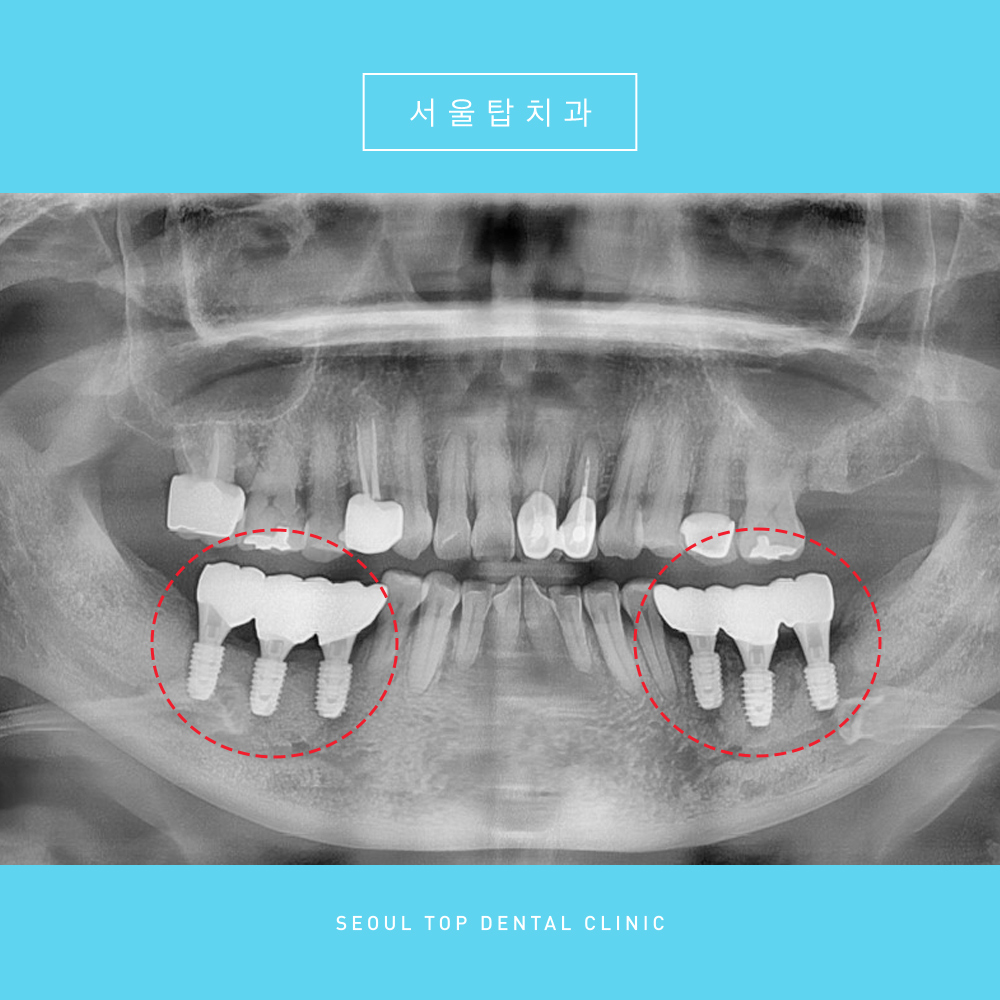

충분한 기반이 갖추어진 후

임플란트 식립을 도와드렸답니다.

현재는 치아 뿌리 역할을 하는

픽스처만 식립된 상태이며,

픽스처가 잇몸뼈에 잘 유착 할 수 있도록

충분한 시간을 기다린 후

치아 머리 역할을 하는

크라운 (보철물) 을 올려주게 됩니다. ^^

치아 머리 부분까지 올려드린

치료 종결 후 파노라마 사진입니다.

🦷 치료 전-> 후